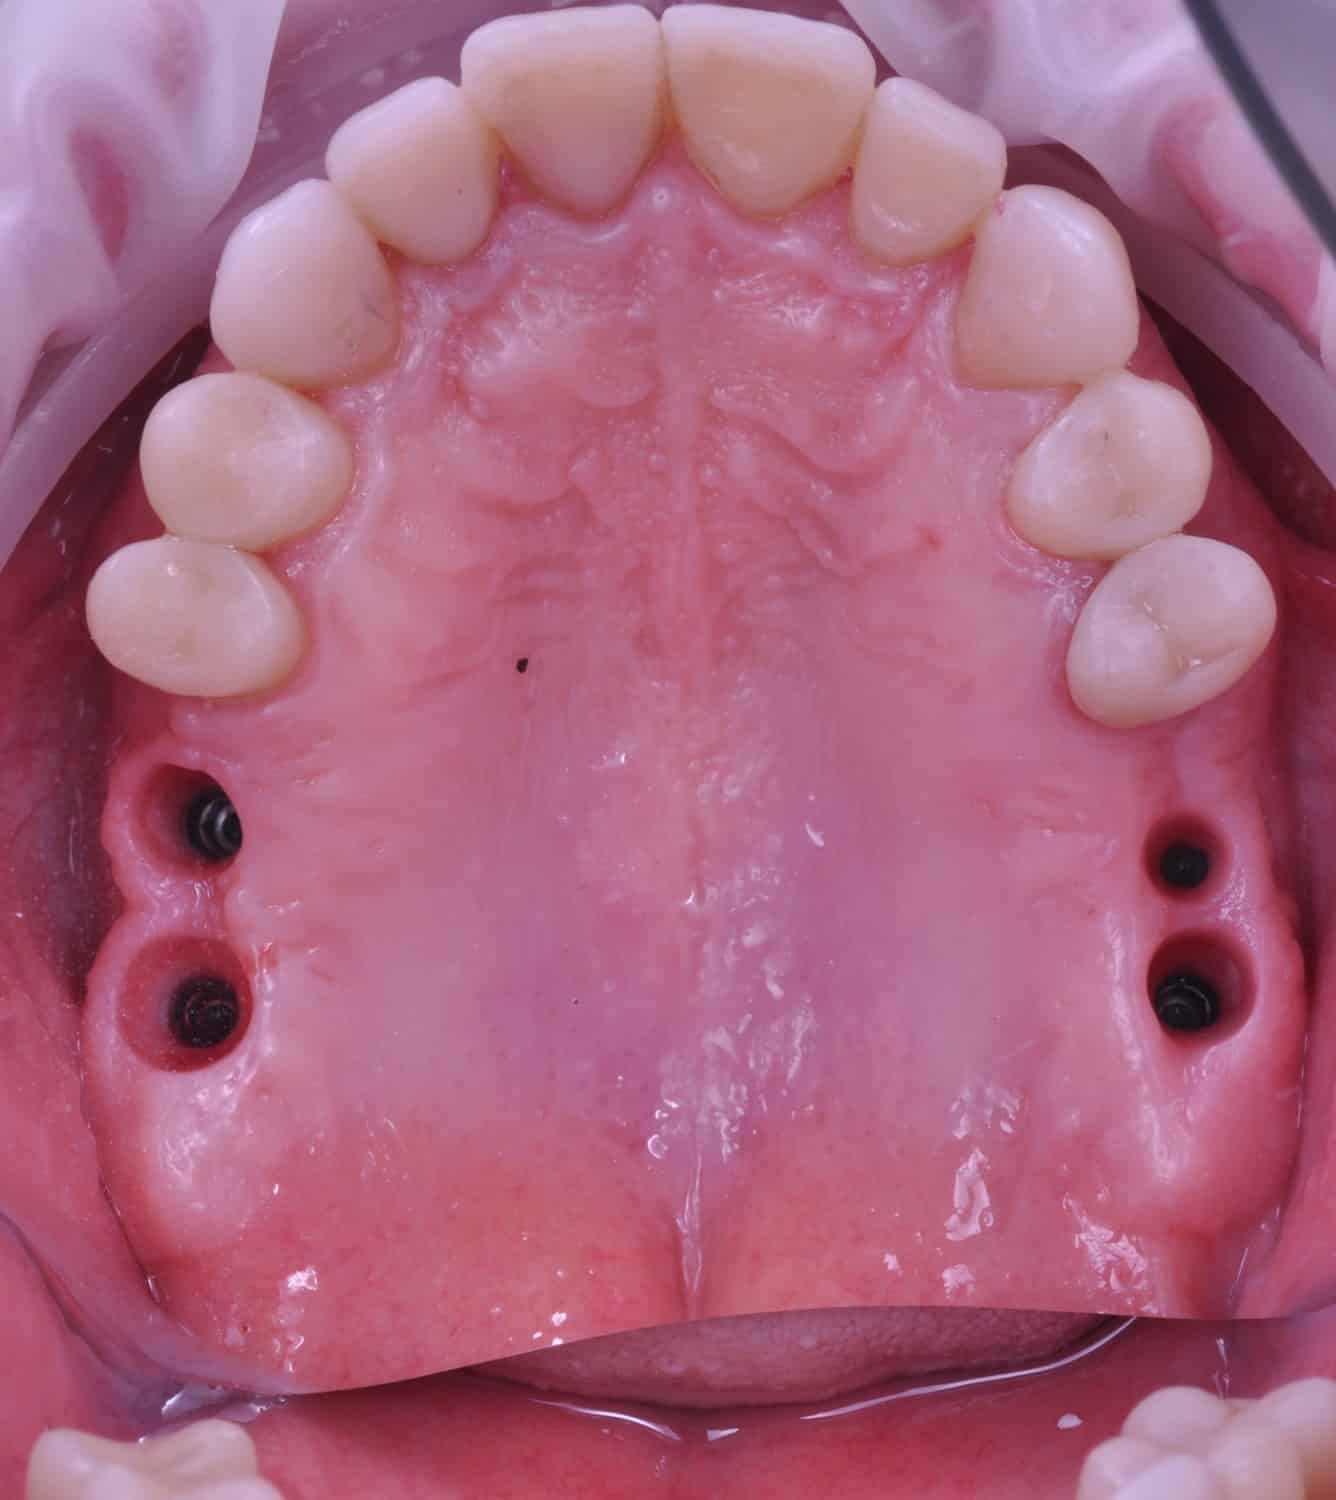

Împreună cu pacientul, am optat pentru inserarea implantelor cu ajutorul ghidului chirurgical pentru a plasa implantul în poziția protetică ideală și pentru a permite realizarea coroanelor insurubate pe implant. A fost efectuată scanarea digitală a arcadelor și a ocluziei pacientului, iar împreună cu tehnicianul radiolog de la DigiRay a fost suprapus fișierul .stl al amprentei digitale peste fișierul .dcm de la CBCT, utilizând software-ul 3Shape.

S-a planificat individual poziția și axul de inserție al fiecărui implant.